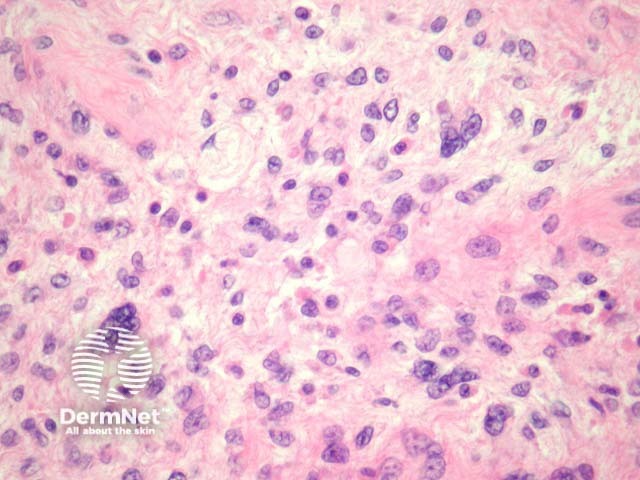

Pleomorphic liposarcoma may be may be difficult to recognize as being lipomatous in origin (figures 6, 7). These are composed of frankly atypical mesenchymal cells often with numerous mitoses and necrosis.

Figure 6

Figure 7